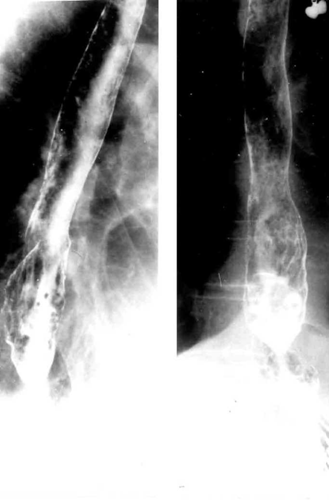

- צילום ושט לאחר בליעת בריום הוא בדיקה פשוטה ביותר, אך דורש ביצוע נכון על-ידי שיקוף החולה בתנוחות שונות, כולל טרנדלנבורג וכן מאמץ של שיעול או ביצוע תרגיל על-שם Valsalva. דיוקה של שיטה זו אינו גבוה מ-45%-40%, ומידת דיוקה באבחון דלקת הוושט אף פחותה. למרות חוסר המהימנות מומלצת בדיקה זו כצעד אבחנתי ראשוני להערכת מצב הוושט, וכמקור מידע בדבר עיוותים אנטומיים בוושט (תצלומים 12.1 ו-13.1).